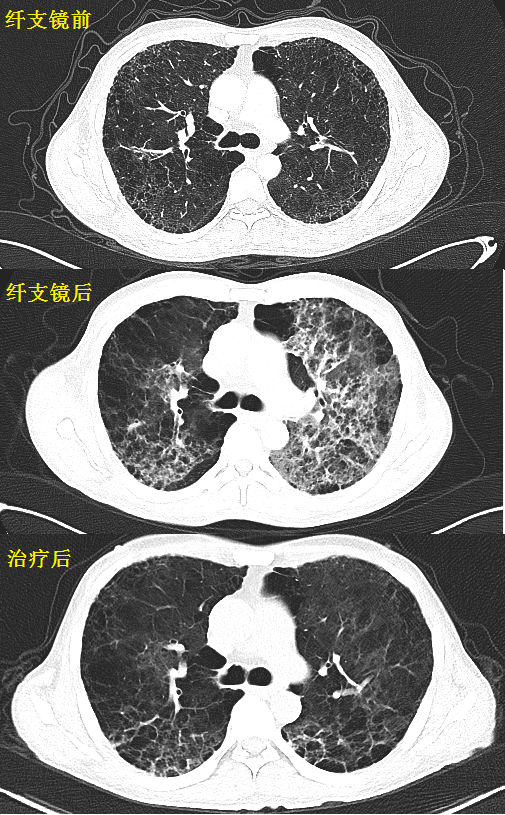

百草枯肺纤维化